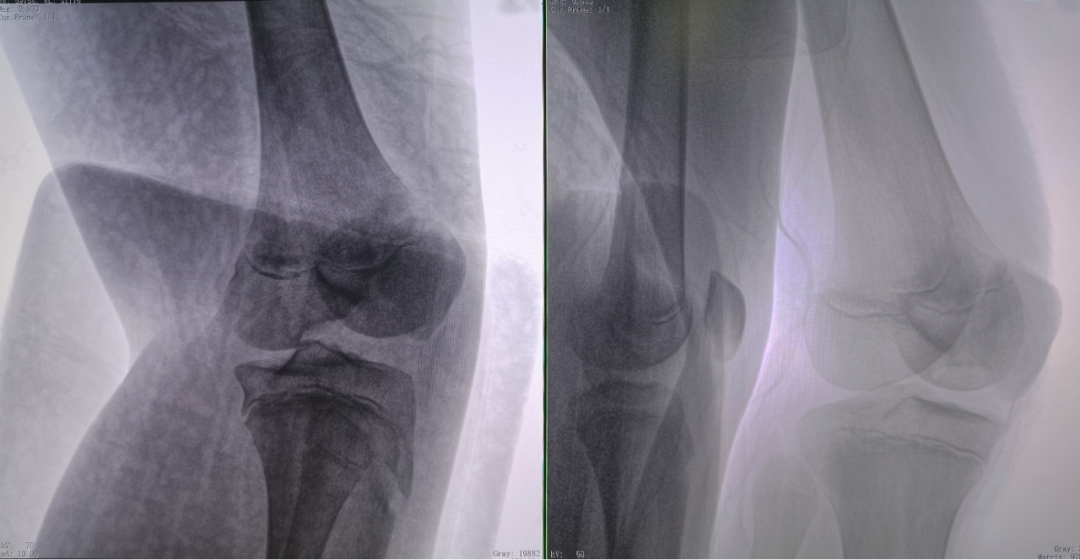

病例2 踝关节骨折复位(31岁)

在踝关节骨折复位手术中,用三维C可以更好地观察骨折部位的复位情况:

正侧位影像观察胫腓联合复位良好

从三维影像看,复位欠佳,贴合度不够